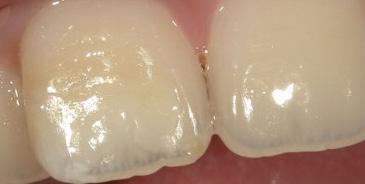

Icon’s

Caries Infiltrant: Revolutionize the way you

caries

Icon

treat early

revolutionary caries infiltration system has been proven to effectively treat interproximal and smooth surface lesions. Offer patients a less-invasive solution to treat early caries with no drilling or anesthesia, in one visit!

more about caries infiltration at: www.drilling-no-thanks.info Buy 1 Icon Cube, Get 1 Icon Etch Refill, FREE! A smile ahead together Initial clinical situation After Icon Smooth Surface Offer for Icon Smooth Surface or Icon Proximal Cubes. To redeem free goods, email your paid Burkhart Dental invoice to freegoods@dmg-america.com, indicating shade of free good. Each qualifying purchase must be submitted within 30 days. Cannot be combined with other offers and may change or be discontinued at any time without notice. Limit 5 per dental Experience all the feels Experience the feel of SILK. Experience a new level of COMFORT. True Comfort ® blu Polychloroprene Examination Gloves A new breakthrough in chloroprene polymer technology delivers improved wet grip, increased touch sensitivity and silky smooth comfort. Each case sold donates to help protect the world’s water. match. 100 GLOVES / BOX NEW Offers valid: 4/1/2023 to 6/30/2023 BUY 8 BOXES, GET 2 BOXES FREE! No mix & match X-Small 22850124 Small 22850126 Medium 22850127 Large X-Large Request Samples at: trydashgloves.com MEDICAL GLOVES Your Trusted Choice in Gloves No mix & match Alasta® 100 100 GLOVES / BOX 22850063 22850060 Medium 22850058 Large 22850061 X-Large 22850006 300 GLOVES / BOX X-Small 22850097 Small 22850098 Medium 22850099 Large 22850100 X-Large 22850101 BUY 8 BOXES, GET 2 BOXES FREE! No mix & match Flexible, Thin Formulation • 300 gloves per box GloveUP® Examination Gloves Alasta® 200 200 GLOVES / BOX X-Small 228500115 Small 228500116 Medium 228500117 Large 228500118 X-Large 228500119 BUY 9 BOXES, GET 1 BOX FREE! ® Soft Fit Nitrile Examination Gloves Extreme Comfort, Precision Fit. A top choice among dental professionals. No mix & match 22850129 22850128 18 // BURKHART DENTAL SUPPLY

Learn